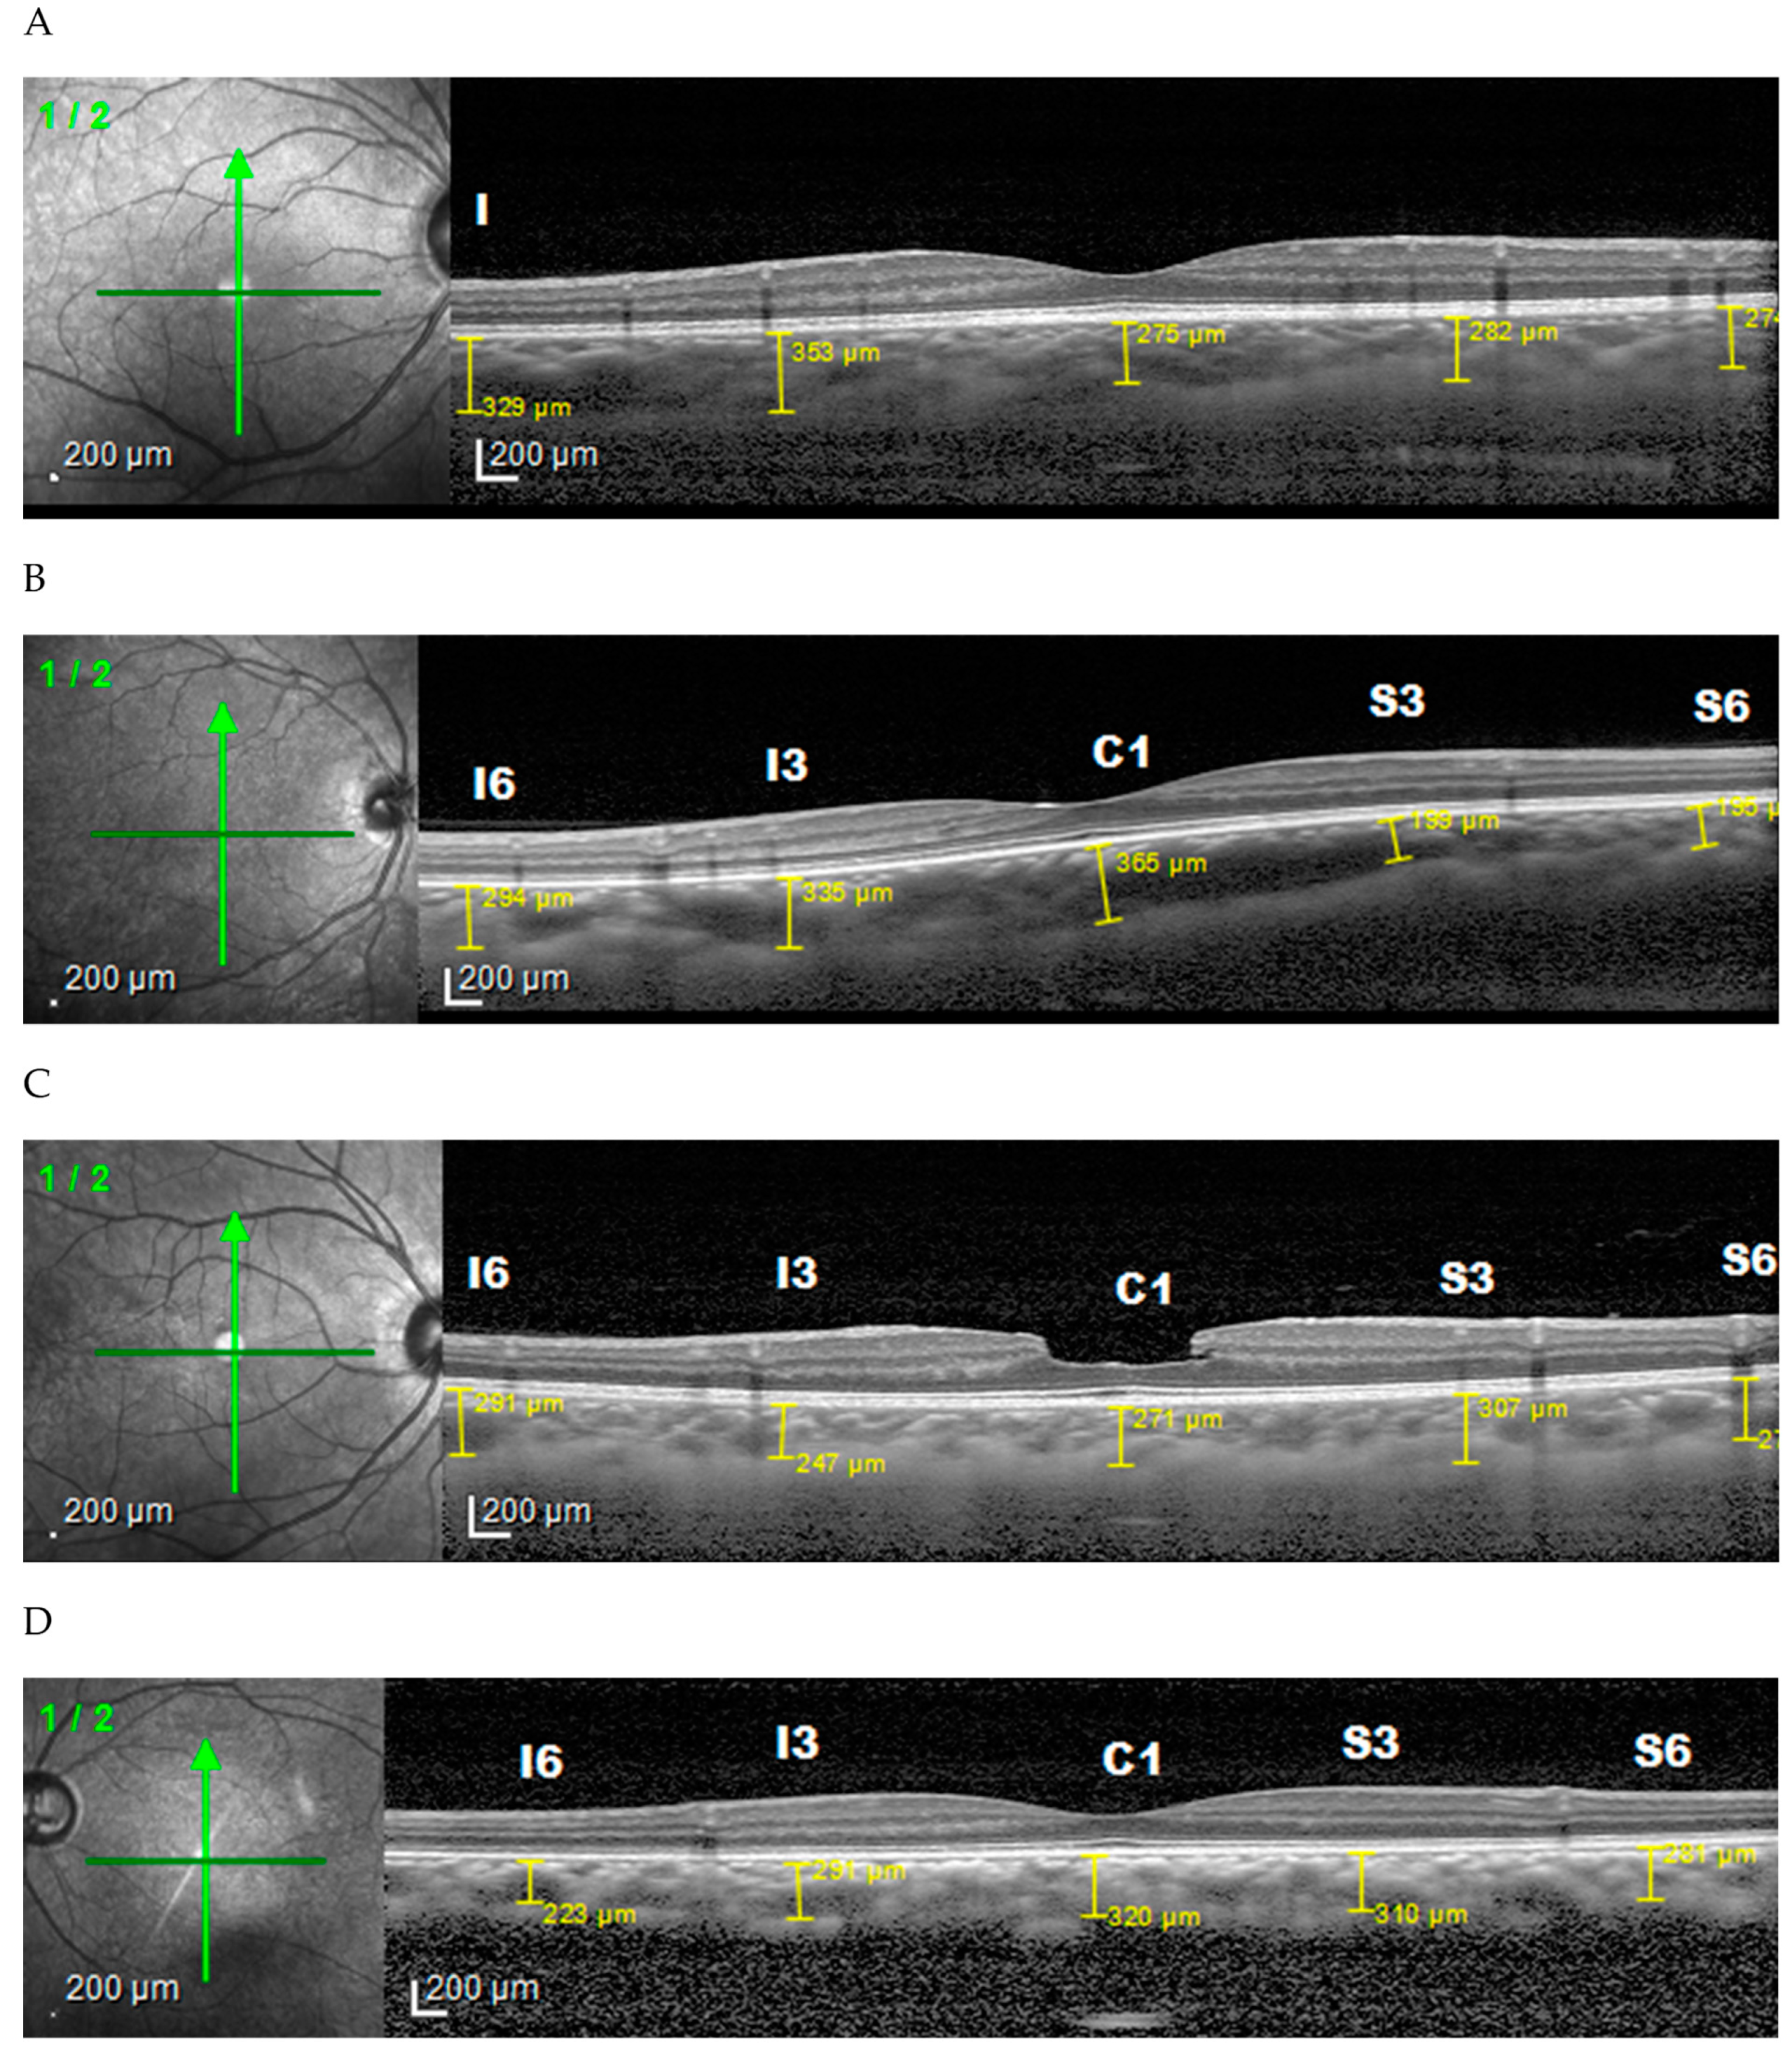

3. Results